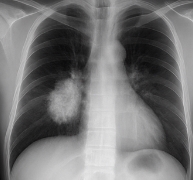

폐암 초기증상이 의심된다면 지체하지 말고 병원에서 검진을 받아야 합니다.

- 흉부 X-ray 검사: 폐 구조 확인.

- 저선량 CT 검사: 조기 폐암 진단에 효과적.

- 세포검사: 가래나 기관지 세포를 검사해 암세포 여부 확인.

폐암 초기증상 발견 시 빠른 진단이 생존율을 크게 높입니다.